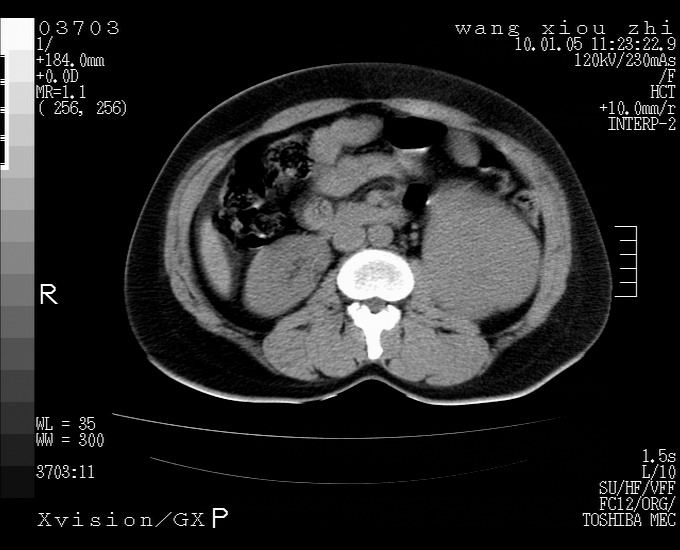

标题: CT23996:f,40.B超提示肿物。 [打印本页]

标题: CT23996:f,40.B超提示肿物。

左肾体积增大!下极见一密度略高团状软组织影!肾周结构组织未见明显异常!考虑左肾占位!建议增强!病史?

左肾占位性病变,建议增强。

实性影 肾癌

左肾占位性病变,考虑肾癌,建议增强 。

左肾占位,肾门及腹膜后淋巴结肿大,考虑透明细胞癌可能性大,建议增强